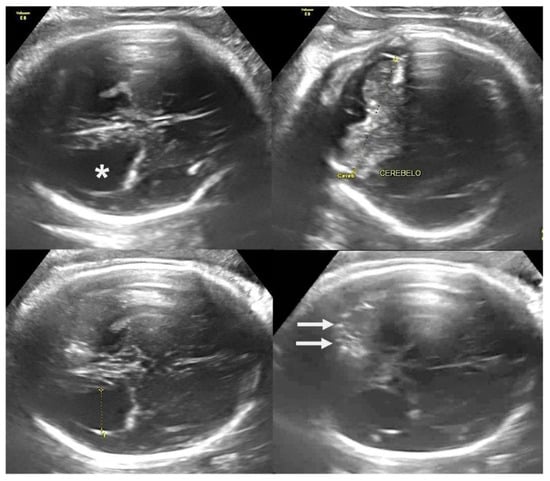

- Araujo Júnior, E.; Carvalho, F.H.; Tonni, G.; Werner, H. Prenatal imaging findings in fetal Zika virus infection. Curr. Opin. Obstet. Gynecol. 2017, 29, 95–105. [Google Scholar] [CrossRef] [PubMed]

- Souza, A.S.R.; Souza, A.I.; Faquin, S.L.L.; Santos Neto, O.G.; Honorato, E.; Matos, A.G.L.; Holanda, S.C.; Figueiroa, J.N.; Schettini, J. Altered intrauterine ultrasound, fetal head circumference growth and neonatal outcomes among suspected cases of congenital Zika syndrome in Brazil. Rev. Bras. Saúde Mater. Infant. 2016, 16 (Suppl. S1), S7–S15. [Google Scholar] [CrossRef][Green Version]